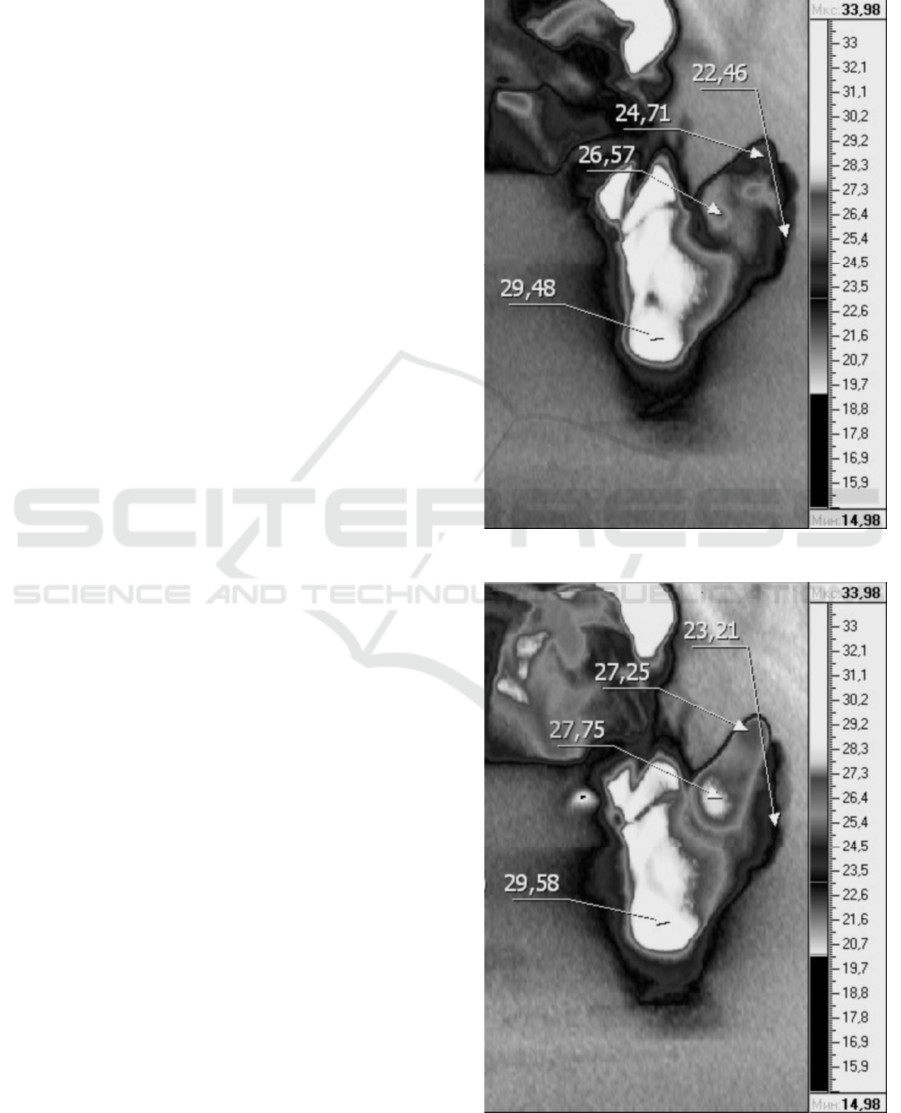

insufficiency. To investigate changes in limb

circulation in two patients with PAD, a study was

carried out using a thermal imager (IRTIS-2000,

Russia).

The surface temperature of the skin, especially

the limbs, measured by the thermal imager varies

greatly depending on many factors. The

experimental conditions (external temperature and

long-term adaptation to the lying position) were

selected in such a way as to minimize the natural

temperature drift as much as possible.

The results of a typical experiment are shown in

Figure 11and Figure 12.

The temperature of the toes increases markedly

10-30 minutes after the start of the procedure (up to

1-2 ° C). In addition, preliminary data show that the

temperature of the feet increases after a course of

procedures. An increase in foot temperature

indicates an integral increase in blood circulation.

Figure 11: Thermal image before exposure.

Figure 12: Thermal image (30 min after start of exposure).